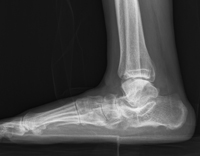

| 수술전 |

수술후 |

| 심한 편평족에서 외측 종골 연장술 및 설상골 열린 절골술의 X-ray |